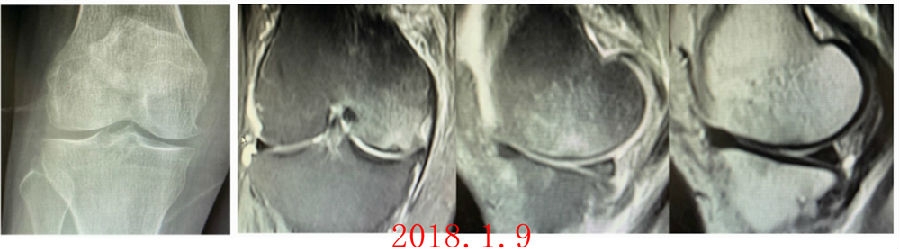

病例1:女,65岁,主诉右膝关节内侧疼痛1周。2018年1月X光未见右膝骨质异常,MR检查见股骨内侧髁骨坏死,半月板相对突出百分比(RPE)28.99%,关节线会聚角1.4°。

予切开行克氏针钻孔减压,口服消炎止痛药物、钙剂及骨化三醇,不负重6周,后改部分负重至3个月。2018年4月复查MR见骨髓水肿基本完全吸收,坏死区局限并修复良好,半月板相对突出百分比(RPE)32.08%,患者临床症状消失。